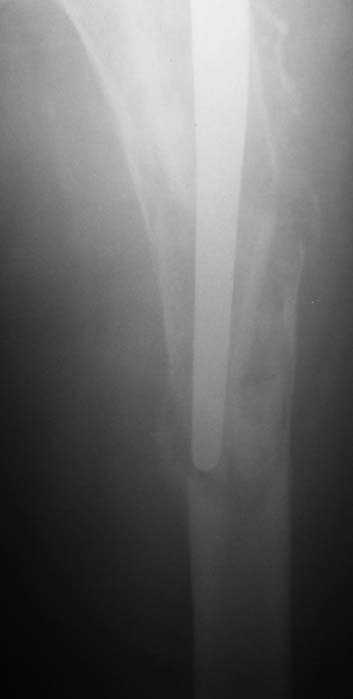

Мужчина, 39 лет.По поводу двустороннего асептического некроза головок бедренных костей последовательно выполнено тотальное эндопроезирование левого (1998 г), затем правого (1999 г) тазобедренных суставов.

11/07/04

С 2001 г отмечает нарастающие боли в левом бедре. Предполагается удаление протеза, удаление цемена из канала бедра, пластика дефекта бедренной кости.

Вторым этапом - тотальное бесцементное протезирование. Ваши предложения, мнения?